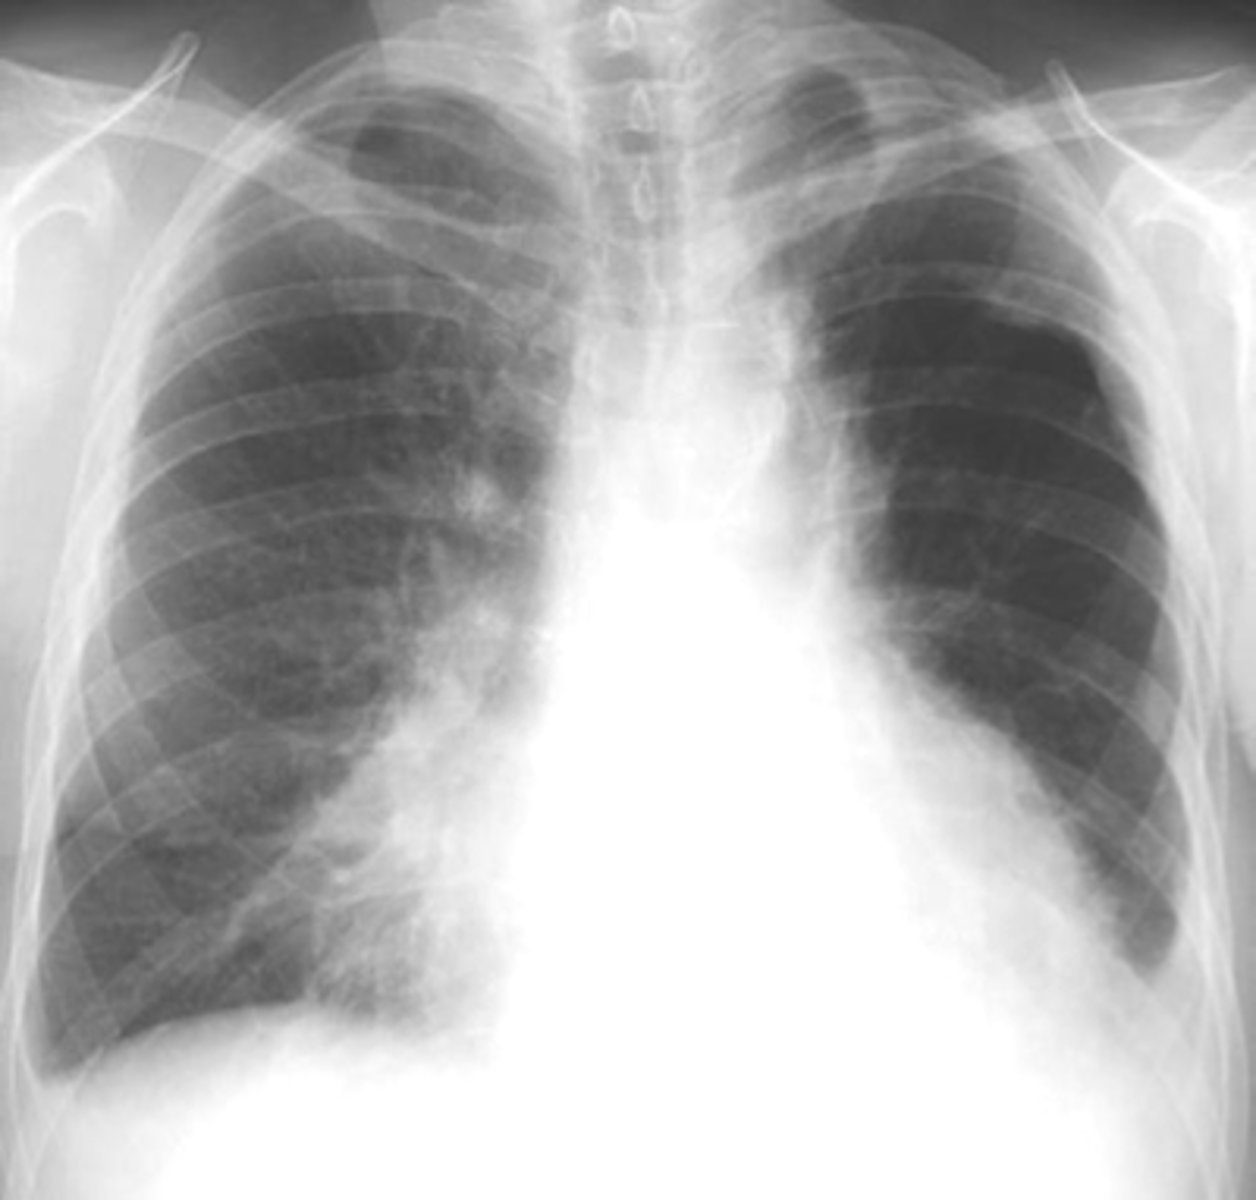

Bilateral pleural effusion